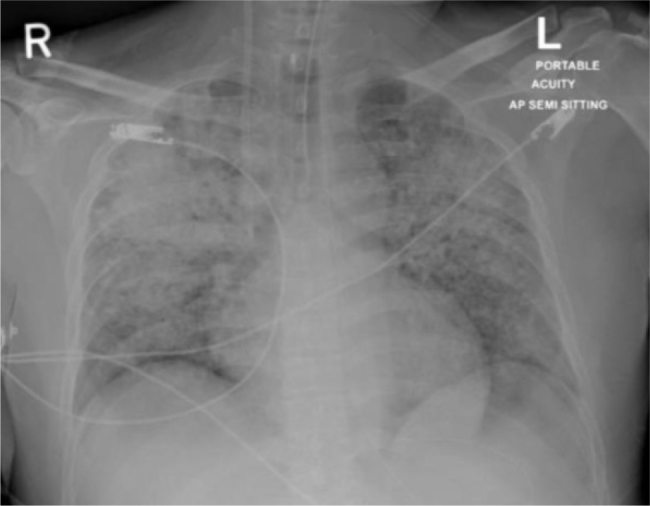

Case report: We present a case of a JW with severe COVID-19 infection and multiple organ failure necessitating ECMO support for 20 days. We discuss the management challenges in patients who do not accept blood transfusions. A significant drop in the patient's haemoglobin and platelet count was observed throughout ECMO duration. An anti-coagulation-free ECMO circuit was maintained, and we did not observe any major circuit or patient complications.